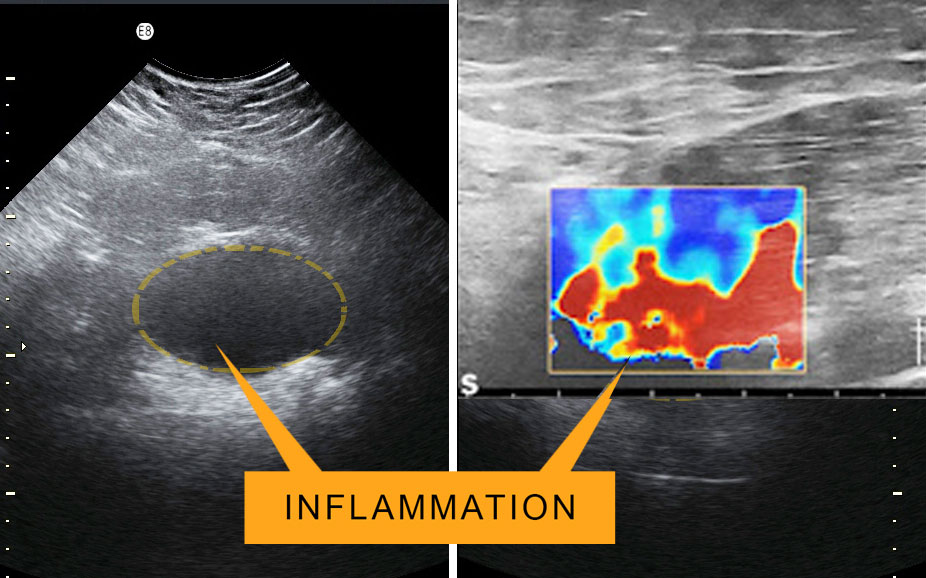

For the many Americans who seek a significantly improved lifestyle or an upgrade in personalized health, getting better answers about our state of health is paramount- and it all starts with DIAGNOSTIC CARE. Especially in hair restorative treatment facilities, studying a patient's scalp and overall health is handled differently. With given teltale signs (such as scarring, inflammation and fungal infection) BardDiagnostics' ScalpScan promotes a fully comprehensive 'deep dive' to a quest for answers about one's hair loss (depending on severity) prior to interventional treatments or procedure.

Hair transplants are considered minimally invasive procedures which often includes bleeding (due to its engagement with large blood vessels or aberrant arteries). Because of this, potential risks may include tapping into unsuspected skin conditions like cancers nearby or underneath- often identified with the use of clinical imaging. The term “scan and treat” is a research term that may also apply to clinical procedures. In the case of IMAGE GUIDANCE, the inclusion of real-time ultrasound monitoring adds a significant layer of safety and added confidence in the technician’s role-- forging a more expedient treatment pace from potential surprises.

During the implant process, there may exist certain LAND MINES like a subcutaneous tumor or a cluster of dilated vessels called a hemangioma that can bleed profusely. Occasionally there may also exist nerves that are traversing the base of the neck or shoulders that may accidentally be damaged in a postoperative situation. Since the micro vessels in the scalp bleed profusely, the formation of a blood clot or hematoma or inflammatory process can also be imaged.

TRAUMA: Soft tissue trauma causes a black and blue area but subcutaneous pathology is best imaged by ultrasound FIG 2 The normal dermal layer is light gray on scans while inflammation is dark gray and fluid (blood) is black. Dermal ultrasound has been used for 30+ years to find skin cancer and guide scar treatment so the use in subacute trauma victims is a logical progression of this portable and non invasive technology.

FIBROTIC SCARRING: Elastography shows scar tissue quantitatively in the liver parenchyma but also in traumatized skin, muscles and tendons. The “elastic” properties of tissue are used worldwide for cancer diagnostics because malignant tumors are rock hard and “gritty” has we feel with the needle biopsy while benign lumps are soft. Ultrasound maps tissue signatures to that free silicone has a MG value 35-40.